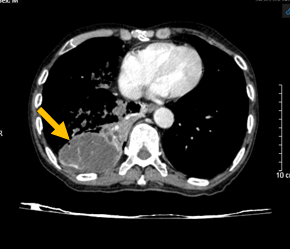

Hình 2: Hình ảnh chụp cắt lớp vi tính ngực – bụng: U thùy dưới phổi phải xâm lấn gan (mũi tên đỏ).

Hình 5: Hình ảnh chụp cắt lớp vi tính ngực – bụng: Nốt tuyến thượng thận bên trái (mũi tên màu đỏ) – theo dõi tổn thương di căn.

Kết luận: Hình ảnh khối u vị trí rốn phổi phải và thùy dưới phổi phải, xâm lấn nhĩ trái gây huyết khối buồng nhĩ trái, xâm lấn thực quản, cơ hoành, nhu mô gan phải. Nốt đặc rải rác phổi trái, hạch trung thất, nốt tuyến thượng thận trái – theo dõi tổn thương thứ phát. Giãn phế nang rải rác nhu mô phổi 2 bên.